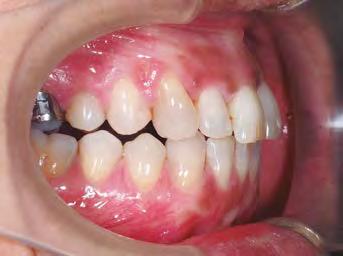

–MARPE, una alternativa a la disyunción en el paciente adulto, por el Dr. Enrique Solano y cols. [88]